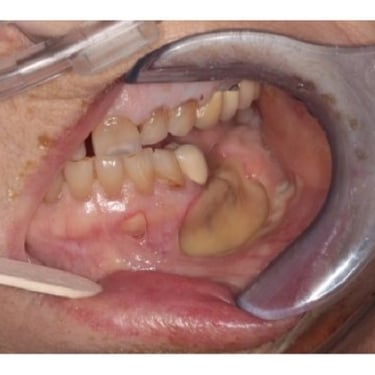

Osteonecrosis de los maxilares

La osteonecrosis de los maxilares es la muerte del hueso mandibular o maxilar debido a una disminución del flujo sanguíneo, a menudo asociada con ciertos medicamentos o radioterapia.

Los pacientes pueden notar dolor, hinchazón y exposición del hueso.

El tratamiento incluye la eliminación del hueso muerto y medidas para mejorar la circulación sanguínea.